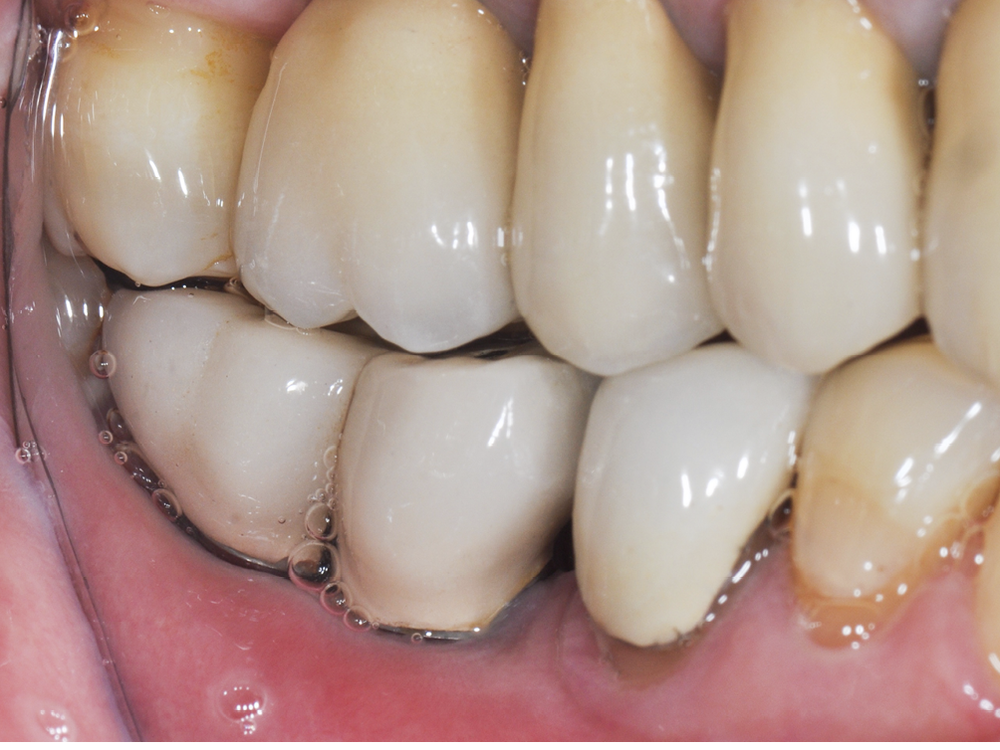

– la péri-implantite définie comme une inflammation des tissus mous péri-implantaires avec une destruction irréversible de l’os péri-implantaire (fig. 2a-b).